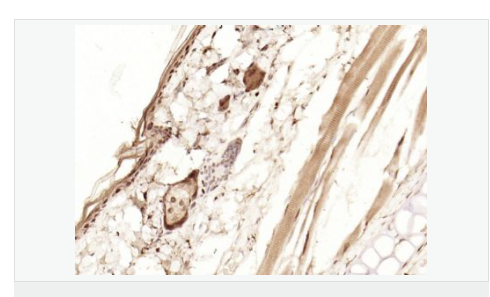

| 产品应用 | WB=1:1000-2000 ELISA=1:1000-5000 IHC-P=1:100-500 IHC-F=1:100-500 Flow-Cyt=1ug/Test ICC=1:100-500 IF=1:100-500 (石蜡切片需做抗原修复) not yet tested in other applications. optimal dilutions/concentrations should be determined by the end user. |